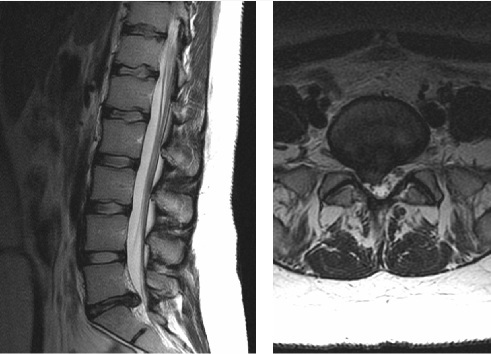

MRI lumbosacral spine dari 23 thn perempuan dengan LBP parah menjalar ke kaki kanannya. Gambar kiri adalah T2 sagital dan gambar kanan adalah axial T2. Nerve root manakah kemungkinan terbesar yg terkompres oleh diskus herniasi?

E. Melintasi S1 nerve roots

The correct answer is the traversing S1 nerve roots.

The MRI shows a focal right paracentral posterior herniation of the L5-S1 intervertebral disc. The herniated disc material causes mild narrowing of the spinal canal and severe narrowing of the lateral recess at L5-S1. The S1 nerve roots traverses at the L5-S1 level, and is therefore the most likely to be compressed by this disc herniation. The traversing L4 nerve root and L5 nerve root have are found at levels above this lesion. The exiting nerve roots at the L5-S1 level (the L5 nerve roots) will already be lateral to the disc herniation and will not be compressed.